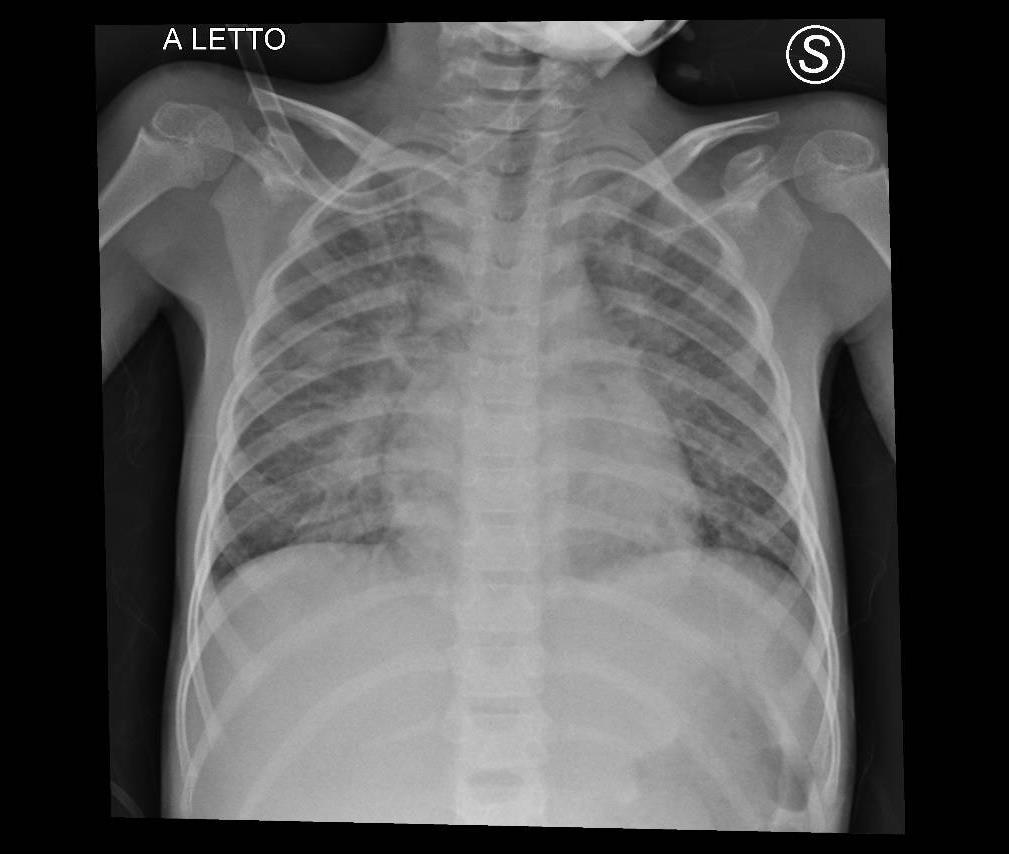

Pediatric COVID-19: MIS-C

Thoracic abnormalities

Cardiovascular abnormalities

Cardiomegaly

CHF or cardiogenic edema

Pulmonary parenchymal abnormalities

Lower lobe atelectasis

Bilateral opacities( ARDS)

Consolidation

Pleural abnormalities

Small pleural effusion

Mediastinal and hilar lymphadenopathy

MIS-C: Heart failure